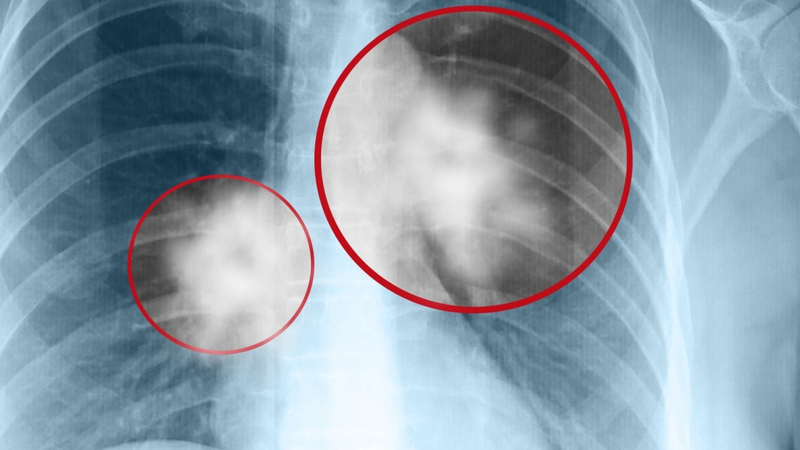

Trước khi chúng ta bàn về tác động của chụp X quang đối với sức khỏe, hãy tìm hiểu xem chụp X quang là gì. Chụp X quang là một kỹ thuật hình ảnh y tế sử dụng tia X để tạo ra hình ảnh của bên trong cơ thể, đặc biệt là xương và mô mềm. Quá trình này giúp bác sĩ chẩn đoán và theo dõi nhiều loại bệnh, bao gồm gãy xương, nhiễm trùng phổi hay cả ung thư.

Một số nghiên cứu đã chỉ ra rằng tác động của tia X có thể gây ra nguy cơ ung thư, nhất là khi tia X tập trung vào một vùng cụ thể trong cơ thể. Nguy cơ này thường nhất quán với việc tiếp xúc lặp lại với tia X, như trong trường hợp của những người làm việc trong lĩnh vực y tế, nơi họ có thể chụp X quang hàng ngày hoặc hàng tuần. Một số nguồn tia X, như tia X CT có năng lượng cao hơn và có tiềm năng gây ra tác động xấu đến sức khỏe hơn.